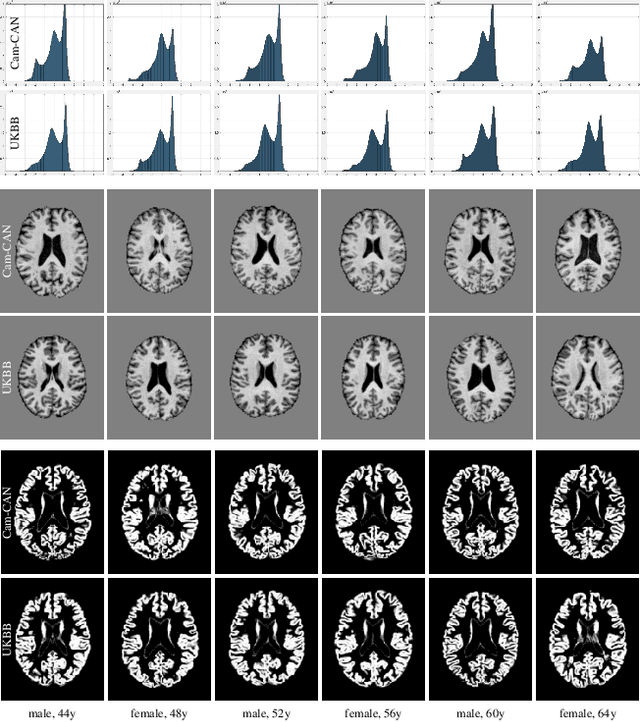

Abstract:This is an empirical study to investigate the impact of scanner effects when using machine learning on multi-site neuroimaging data. We utilize structural T1-weighted brain MRI obtained from two different studies, Cam-CAN and UK Biobank. For the purpose of our investigation, we construct a dataset consisting of brain scans from 592 age- and sex-matched individuals, 296 subjects from each original study. Our results demonstrate that even after careful pre-processing with state-of-the-art neuroimaging pipelines a classifier can easily distinguish between the origin of the data with very high accuracy. Our analysis on the example application of sex classification suggests that current approaches to harmonize data are unable to remove scanner-specific bias leading to overly optimistic performance estimates and poor generalization. We conclude that multi-site data harmonization remains an open challenge and particular care needs to be taken when using such data with advanced machine learning methods for predictive modelling.